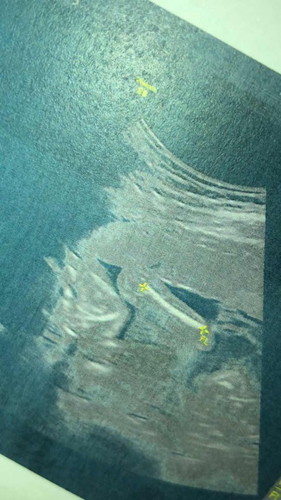

อัลตราซาวด์มาค่ะ แต่น้องนอนหนีบขาไว้ไม่ให้เห็นเลย น้องดิ้นนะคะแต่น้องหนีบขาไว้ตลอด😅😂 แบบนี้จะได้ชายหรือหญิงคะ อยากรู้มากๆค่ะ แม่อยากเอฟชุดรอน้องมากๆแต่น้องแกล้งแม่😂😂

ได้ผู้หญิงแน่ๆเลยค่ะ เพราะเคยมีรุ่นน้องที่รู้จักคนนึงหมอนัดตรวจท้องทีไรก็ไม่ยอมให้เห็นเพศสักที ลุ้นจนวินาทีสุดท้ายตอนผ่าคลอดถึงรู้ว่าเป็นผู้หญิงค่ะ